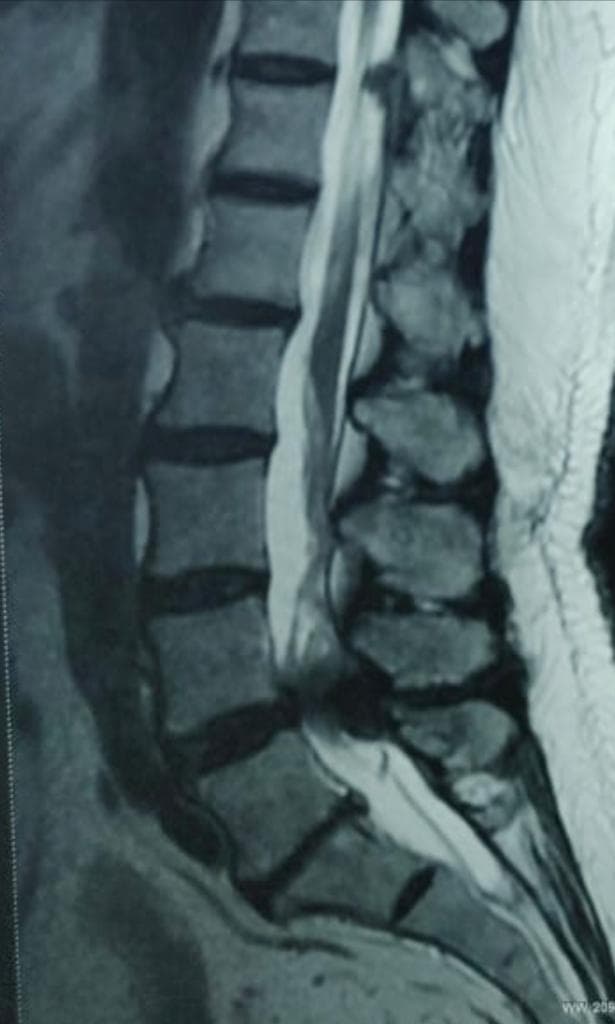

- Spinal canal stenosis is condition of spine where spinal canal become narrow. This put pressure over the spinal cord and nerves passing through it.

The diagnosis depends on complaints and a physical examination. Following are some examples: